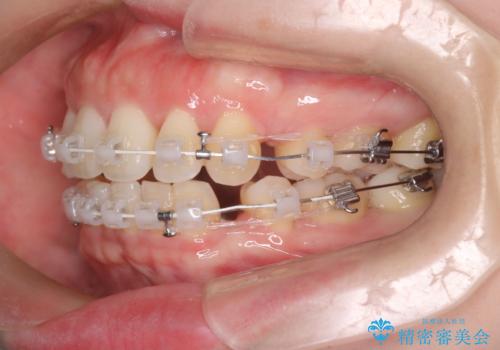

- 矯正装置

- 審美装置

抜歯スペースの移動量を調整するために、矯正用アンカースクリューや親知らずを活用して治療を行いました。